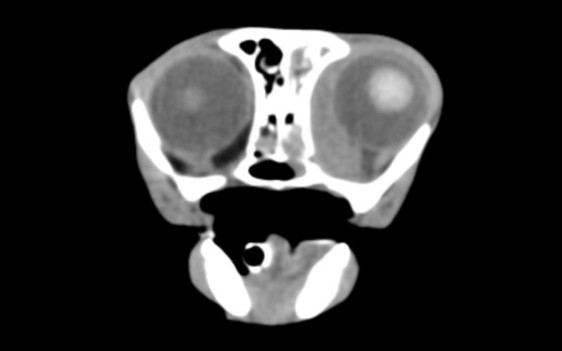

左目の第三眼瞼突出、流涙、鼻汁、鼻閉

診断と治療

CT撮影と組織生検にて大細胞性リンパ腫と診断され、放射線治療と抗がん剤治療の提案をしました。相談の結果抗がん剤治療を行うこととなり6カ月の抗がん剤治療(CHOPプロトコル)を行いました。

before